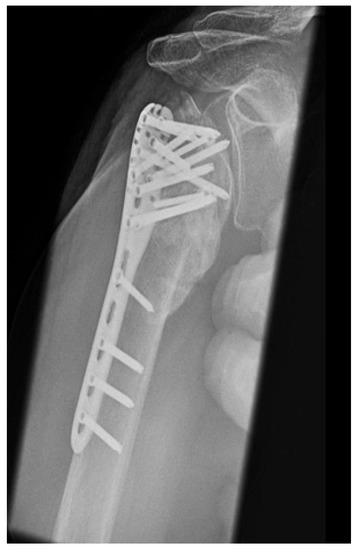

| Complication Type | Exemplary Images by X-rays or Pattern Images | Definition |

|---|---|---|

| 3 | ![]() | Type 3 describes a displacement of the angular stable plate osteosynthesis with screw cutout/fracture avulsion in the humeral shaft region, while the humeral head position remains intact. |

| 4 | ![]() | Complication Type 4a is based on the presence of AVN of the humeral head without concomitant destruction of the glenoid articular surface due to an associated screw cutout through the humeral head cortex. |